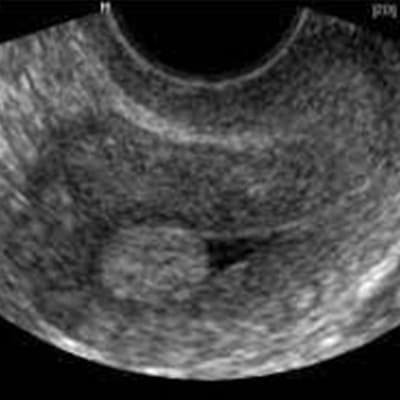

Endometriosis